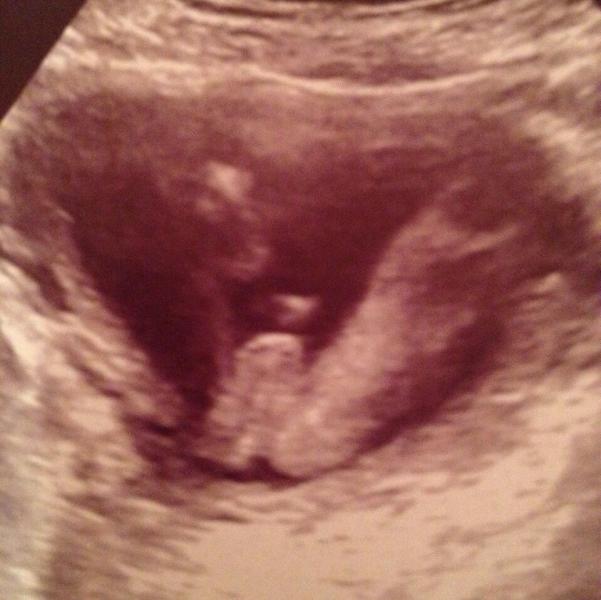

Сегодня ходили на узи , у нас мальчик 👍👶первое что сказала врач глядя на экран , вот это писюнчик!)))

А нам сделали тоже замечание что у нас длинные ножки и большие яйки)) прям гордость )))